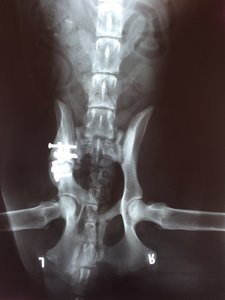

Ich hab mir mal die Röntgenbilder schicken lassen.

Hier sieht man mal den Spalt der nach dem Sturz entstanden war man sieht auch, wie sehr der Beckenknochen in Richtung Wirbelsäule gedrückt wurde :shock:

Hier mal im direkten Vergleich: direkt nach der OP

So sieht es jetzt aus. Knochenmaterial noch etwas "dünn", aber jetzt schon soweit, dass sie absolut nicht mehr humpelt oder hoppelt und auch wieder komplett belastet.